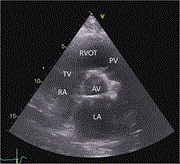

An ambiguous presentation of cardiac calcified amorphous tumor in a 37-year-old male

Mike Ghabally and others

Journal of Surgical Case Reports, Volume 2023, Issue 7, July 2023, rjad397, https://doi.org/10.1093/jscr/rjad397